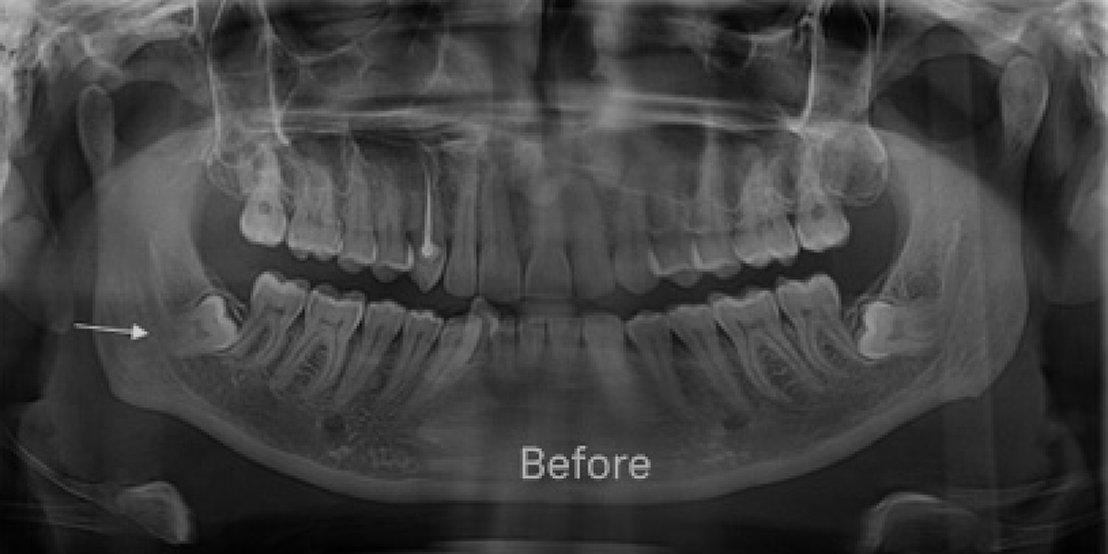

Wisdom Tooth Removal

Whether you need a dental filling Dubai treatment for decay or a dental gap filling to improve aesthetics and bite alignment, our gentle, expert approach protects your teeth and relieves discomfort. We also provide care for wisdom teeth, including safe and effective wisdom tooth extraction Dubai when needed. Count on us to keep your smile healthy, resilient, and looking its best for years to come.